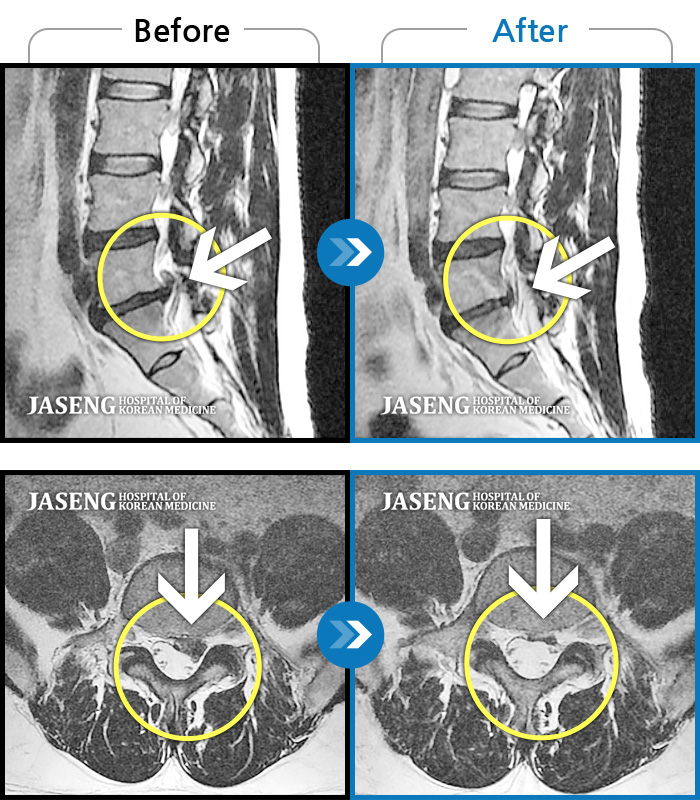

허리디스크

일산 · 김진수 원장

우측 골반 통증이 심하고 우측 하지로 당김과 저림이 지속되었습니다. 야간통이 심하여 야간 수면 제한이 되는 등 중등도 이상의 통증을 호소하는 상태였습니다.

촬영시기

2021.03.22 ~ 2025.09.30

2025.10.30